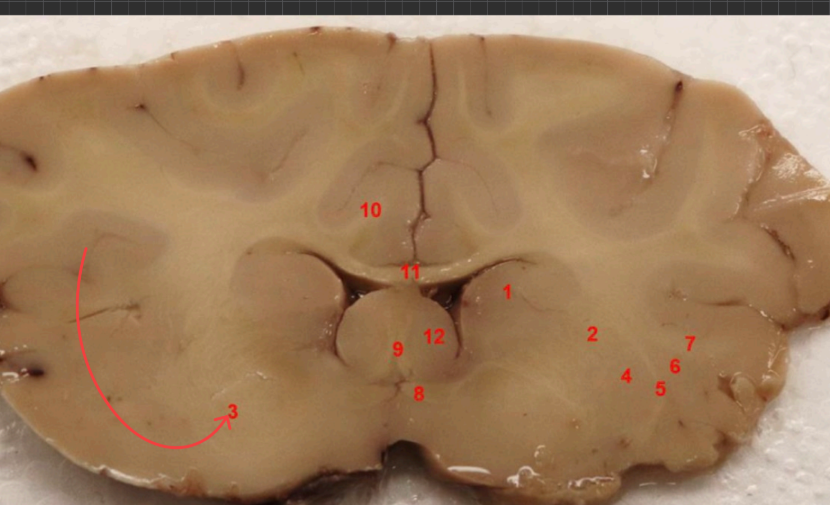

what cortex is this

piriform cortex, part of olfatcory system ( smell)

what area is this

internal capsule

what nuclei is this ? function

Putamen, regulates motor control, including movement initiation, planning, and execution.

external capsule

what is this

claustrum

what area is this?

extreme capsule

what nuclei is this?

Global Pallidus , regulates voluntary movement, suppresses unwanted motor activity, and influences reward/motivatio

what tract is this

Fornix

Global Pallidus

Putamen

Clustrum

Insula, internal sensation (interoception_

what cortex is this?

piriform cortex

columns of fornix

septum

anterior comissure